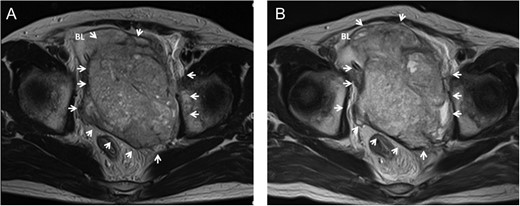

Ten years after the first treatment the patient presented to our department with a complaint of lower abdominal pain. MRI identified a 10 cm mass in the pelvis that had invaded the bladder (Fig. 3A); no other tumor was detected by thoracic and abdominal CT. The AFP, βHCG, neuron specific enolase and HCG levels were 654.9 ng/mL, 1.2 ng/mL, 36.6 ng/mL and 18.8 mIU/mL, respectively. He underwent a transrectal tumor biopsy, and pathological findings identified a GCT consisting of seminoma, teratoma and sarcoma. The patient was diagnosed with late-relapse testicular tumor/teratoma with SM.

Pelvic MRI showing a large pelvic mass invading to bladder before chemotherapy in case 2 (A). The mass increased in size accompanied with worsening of bladder invasion after chemotherapy (B). Arrow, tumor; BL, bladder.

After one cycle of GCT-oriented chemotherapy the tumor had increased in size (Fig. 3B). He underwent tumor resection and cystectomy. Pathological findings revealed a mature teratoma with SM, consisting of rhabdomyosarcoma, glioblastoma and adenocarcinoma, that had invaded the bladder; no seminoma component was found (Fig. 4). The levels of all tumor markers decreased to their normal ranges after surgery. To date, the patient has experienced no relapse for 6 months.